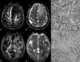

Anaplastic astrocytoma

Anaplastic astrocytoma is a rare WHO grade III type of astrocytoma, which is a type of cancer of the brain. In the United States, the annual incidence rate for Anaplastic astrocytoma is 0.44 per 100,000 people Signs and symptoms Initial presenting symptoms most commonly are headache, depressed mental status, focal neurological deficits, and/or seizures. [Source: Wikipedia ]